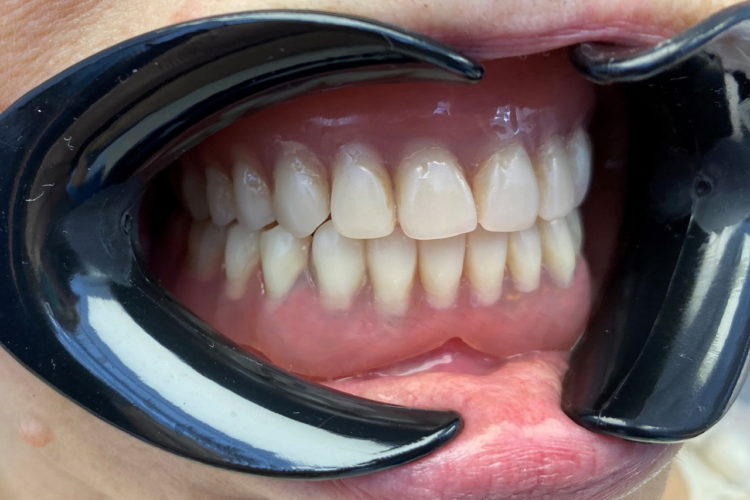

Pacienta in varsta de  65 ani, edentata total la maxilar si subtotal la mandibula la care s-a realizat o reabilitare protetica cu proteze mobile totale, la mandibula primind o supraproteza stabilizata pe magneti atasati unor cape pe dintii restanti. Protezele sunt armate cu plasa metalica individualizata pe forma crestelor restante pentru cresterea rezistentei mecanice a acestora.